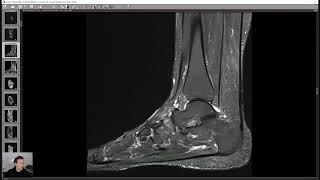

Dr Christoph Agten

I'm PD Dr. med. Christoph Agten, an MSK radiologist, mentor, and teleradiologist. I founded the Virtual MSK Fellowship, helping over 300 radiologists master MSK faster than they thought possible. I have completed fellowships in Zurich and NYU, written 40+ research papers, and published the bestselling books SPEED MSK and THE CONFIDENT RADIOLOGIST.